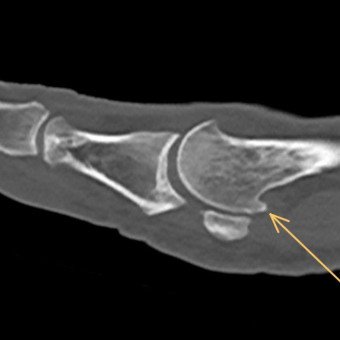

Zur genaueren Untersuchung und Darstellung machten wir daher ein CT, das die Knochen besser darstellt.

Plantarer Osteophyt

Solche Überbeine werden in der Fachsprache als Osteophyten bezeichnet und bilden sich bei beginnenden Arthrosen. Dass diese in eine schmerzhafte Richtung nach unten wachsen ist sehr selten.